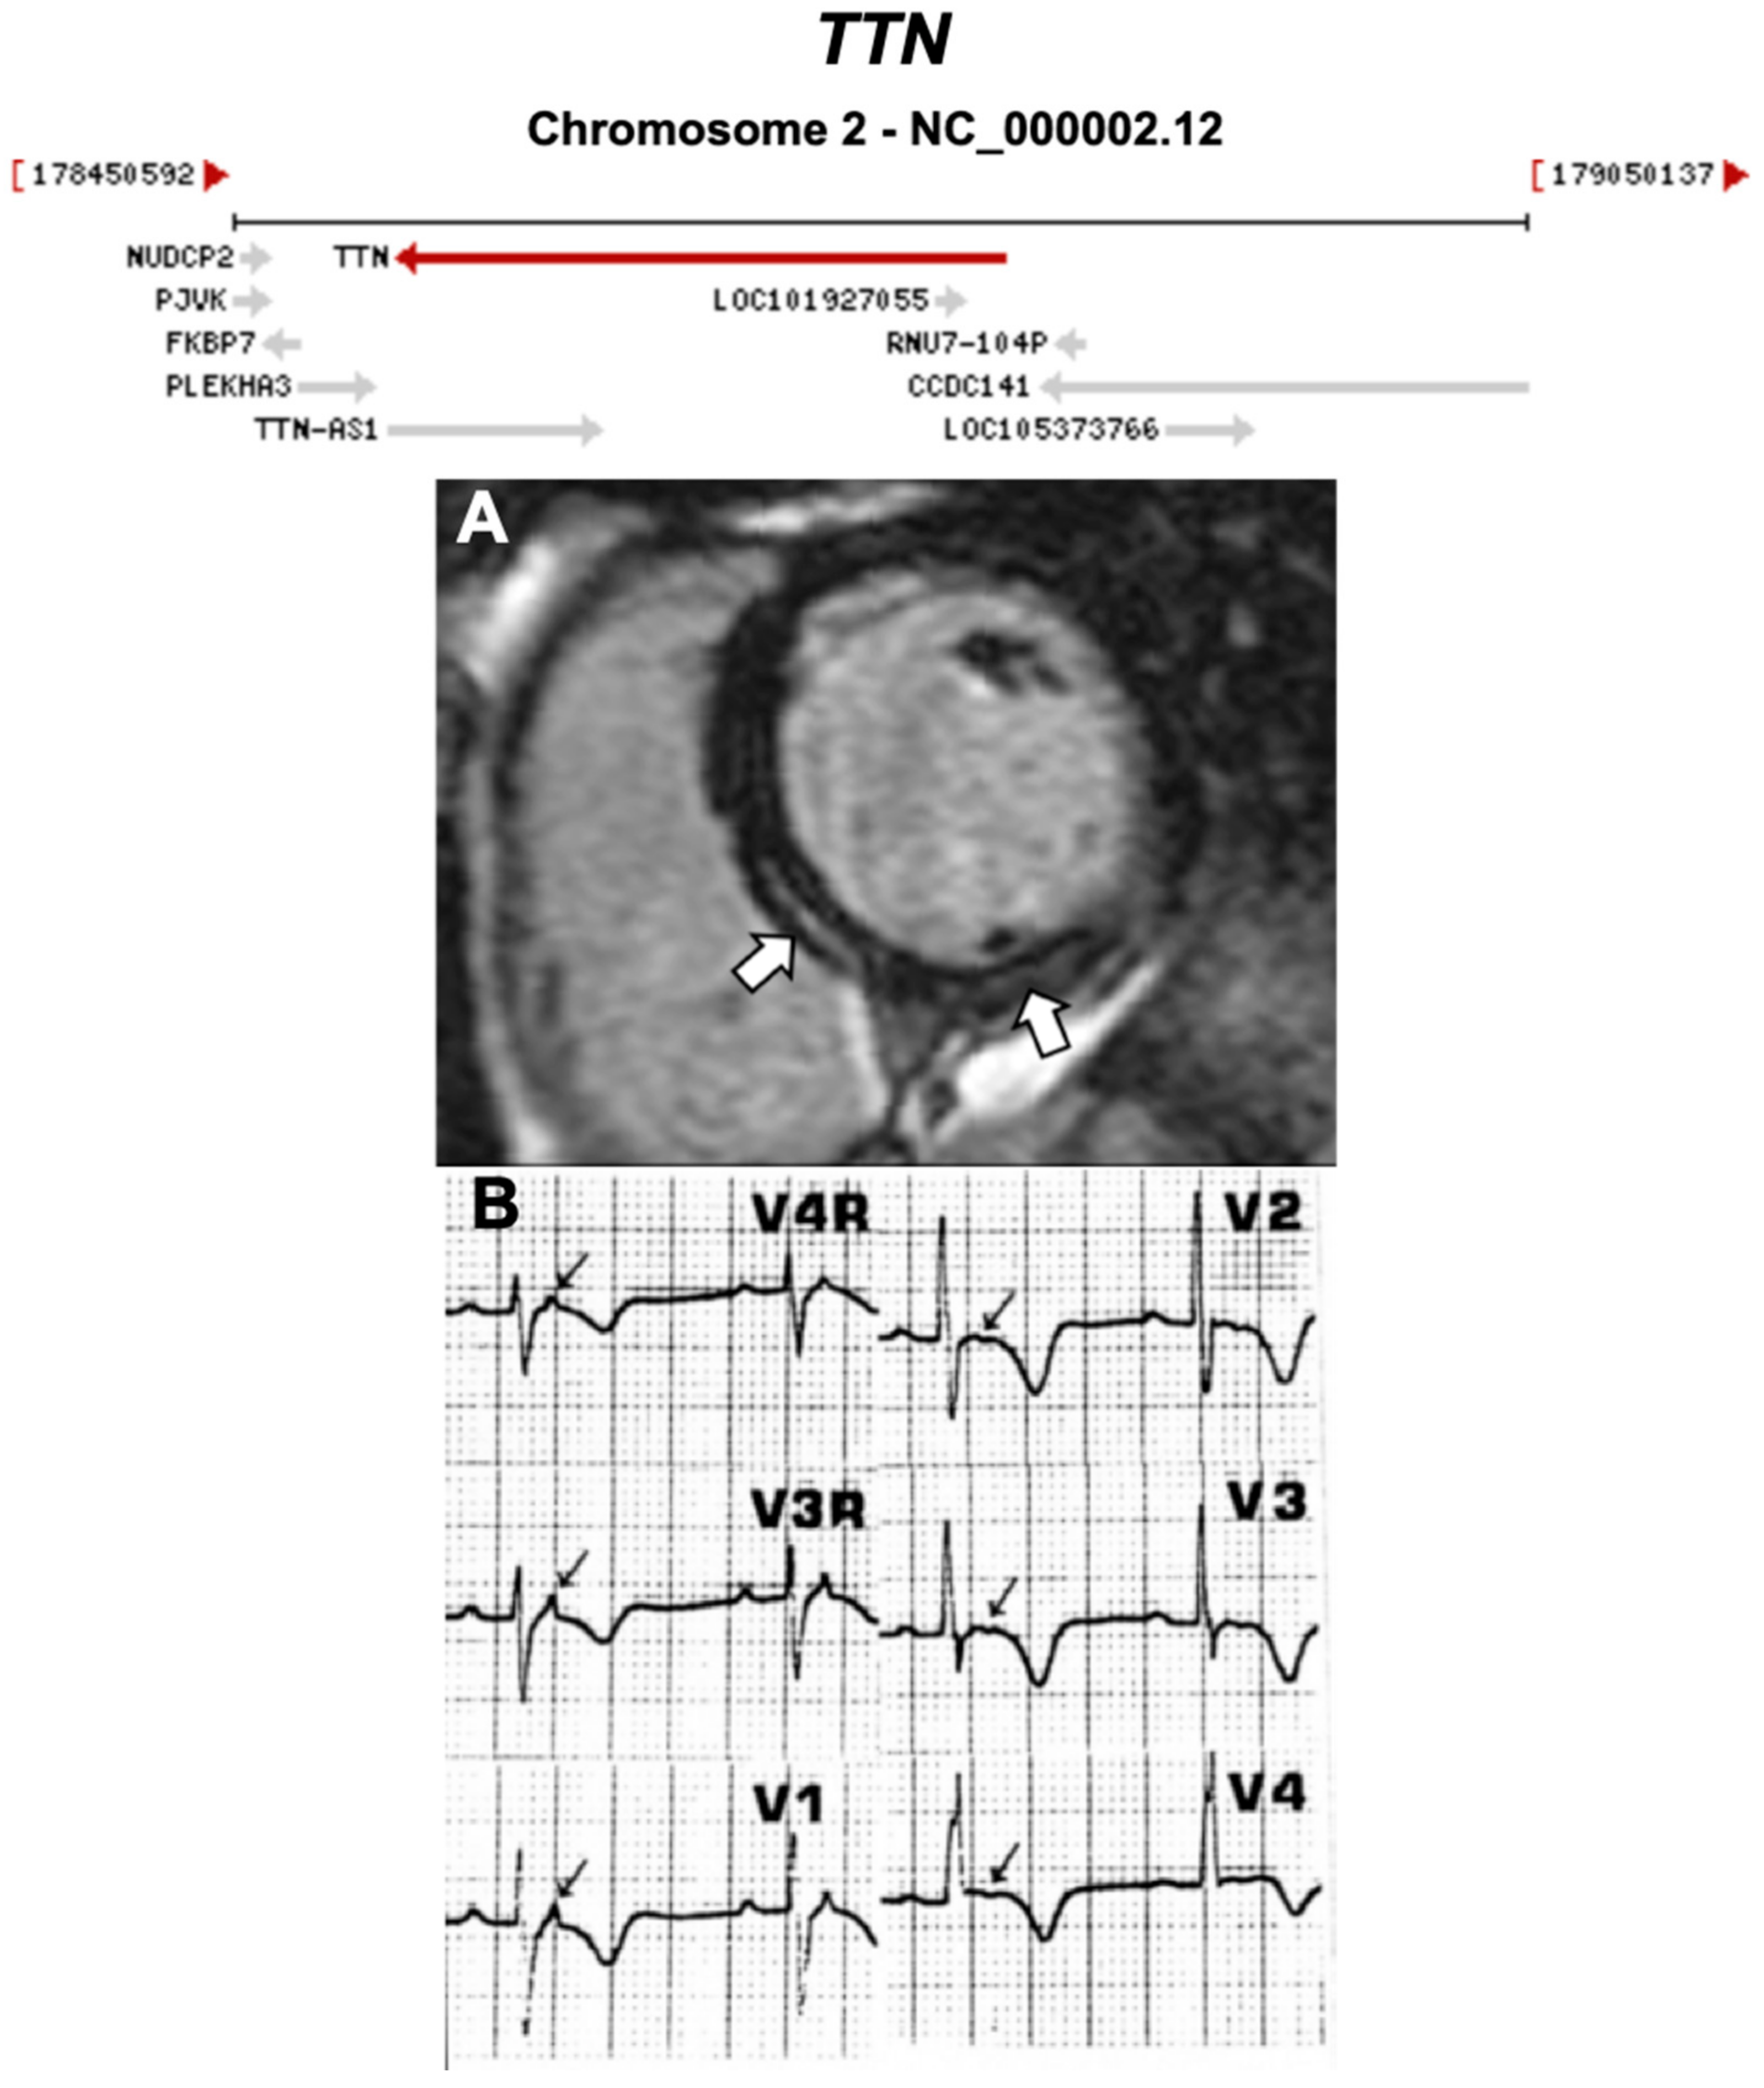

| TTN | Sarcomere | 18% | AD | RV, LV, BIV | - | 2q31.2; 365 | DCM | Limited for ARVC |